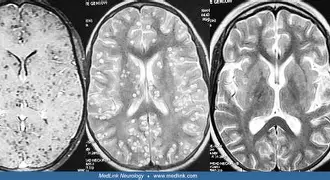

3. Why Does Neurocysticercosis Cause Seizures? | Stages & CT Signs Explained by Dr. Anand Bhatia

If you still get confused with NCC stages, this is the session you need.

What makes this session unmissable:

– VCGN classification (Vesicular → Colloidal → Granular → Nodular)

– The ONLY stage where seizures actually happen (very important)

– “Hole in Dot” sign – a classic exam favorite

– CT/MRI findings across all stages

– Simple memory tricks for long-term retention

Neurocysticercosis